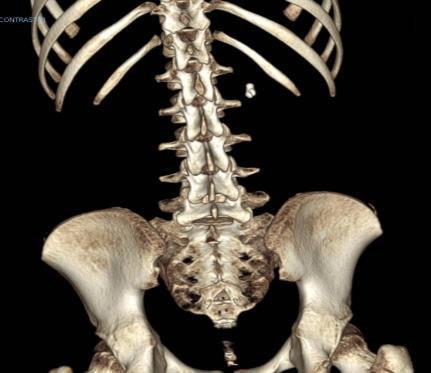

SDR involves surgically accessing the spinal cord (typically in the lumbosacral region, L2 to S1 or S2).The dorsal (sensory) nerve roots are carefully identified and then divided into smaller bundles called rootlets.

T10–12 spastic diplegia

C5–T2 spastic quadriplegia

C1–C4 secondary generalized dystonia